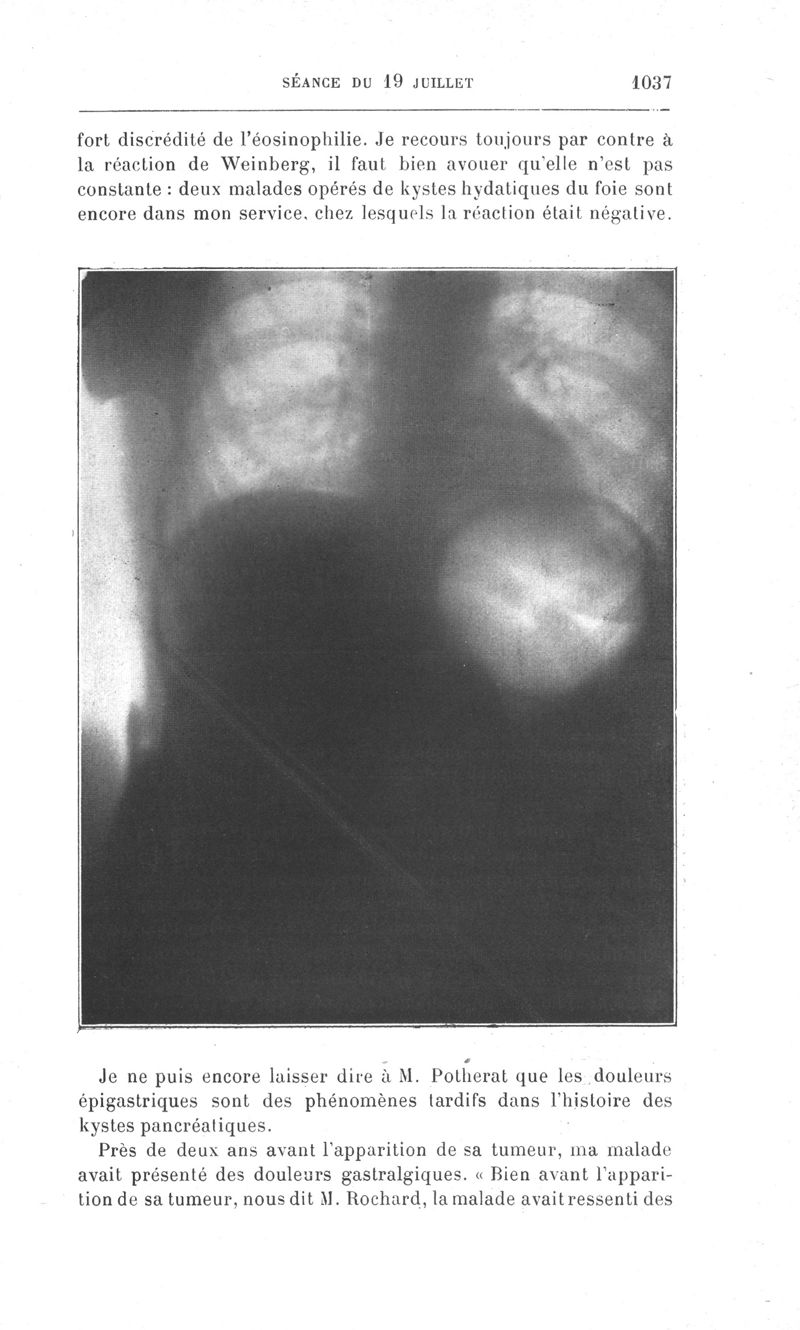

Bulletins et mémoires de la société de chirurgie de Paris

Tome XXXVII, 1911. - Paris : Masson, 1911.